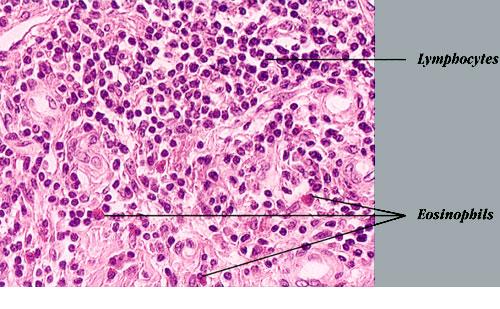

Histopathologically, the dermis and/or subcutis exhibit hyperplasia of small blood vessels lined by plump endothelial cells similar to those present in the high endothelial venules of lymphoid tissues. These venules are a major point of lymphocyte trafficking between the blood and the paracortical T-cell domain of lymph nodes. Surrounding these hyperplastic vessels is a dense infiltrate composed of small lymphocytes, plasma cells, histiocytes, and eosinophils. The latter are typically prominent but may be absent in some cases. There are usually multiple secondary lymphoid follicles with prominent germinal centers, particularly in the subcutaneous lesions. In general, lesions are more superficial and the vascular features are more prominent in AHLE, whereas lesions are deeper and the lymphoid features are more prominent in Kimura disease.